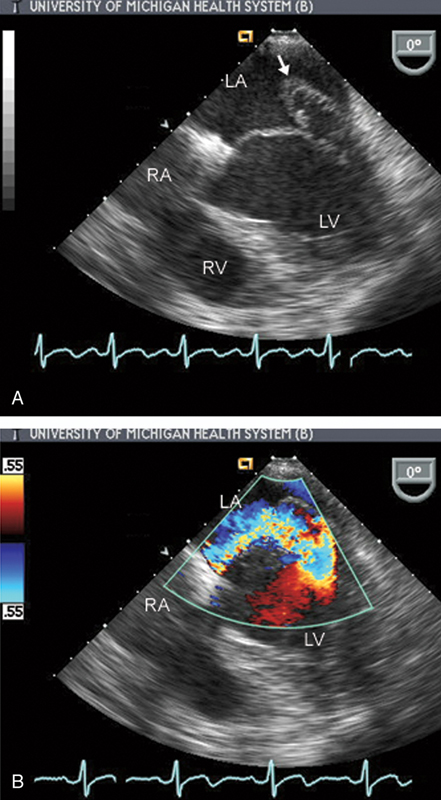

فحوصات تشخيصية لبعض امراض القلب والشرايين التاجية